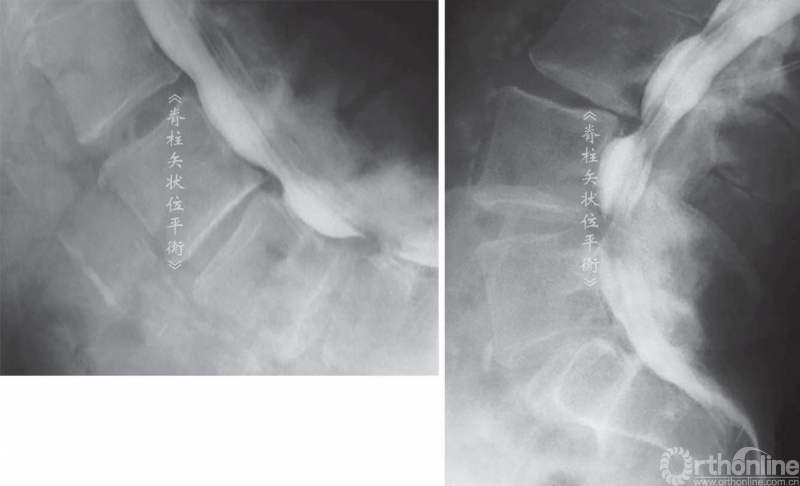

骨关节炎性的椎管狭窄导致伸展时(或前凸)比屈曲时(或后凸)出现更多的症状。不考虑椎管水平因素时,椎管前后径伸展时减小,屈曲时增大。同时,根据神经根的运动原理,神经根屈曲时向椎体前方运动靠近椎体和椎间盘,伸展时向后运动靠近后方椎弓(图8,图9)。

这也解释了颈椎伸展时会加剧压迫性、骨关节炎的颈、臂部的疼痛症状,腰椎屈曲或后凸时可改善腰椎管狭窄引起的神经源性跛行。伸展站立位X线不注射或注射造影剂(脊髓造影术)可证明这种动态受压的过程(图9,图10)。

脊柱后凸会挤压神经引起相应的症状,多见于腰椎管狭窄症。间歇性跛行是继发于椎管狭窄的一种临床症状,在处于伸展位置时加重。一些矢状位失平衡患者可以通过简单的神经根减压术改善其平衡状态。

图9 屈曲(A)和伸展(B)时椎间孔的比较

图10 L3~L4 和L4~L5中央椎管体积减小,伸展位(B)和屈曲位(A)的比较